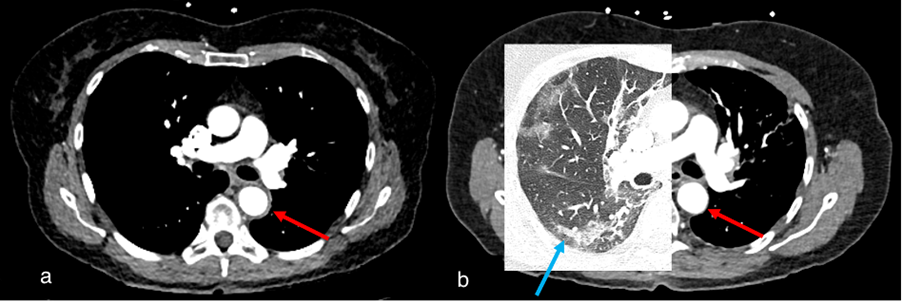

Figure 4.

Case 1, a 67-year-old female. (a) Initial chest CT to clarify pulmonary embolism or post-COVID-19 findings showed concentric wall thickening of the thoracic aorta (red arrow), indicating large vessel vasculitis. No pulmonary infiltrates or post-COVID-19 findings were observed. (b) Follow-up computed tomography 2 months later showed indeterminate appearance of recurrent COVID-19 pneumonia (blue arrow) and regressed arterial wall thickening (red arrow).